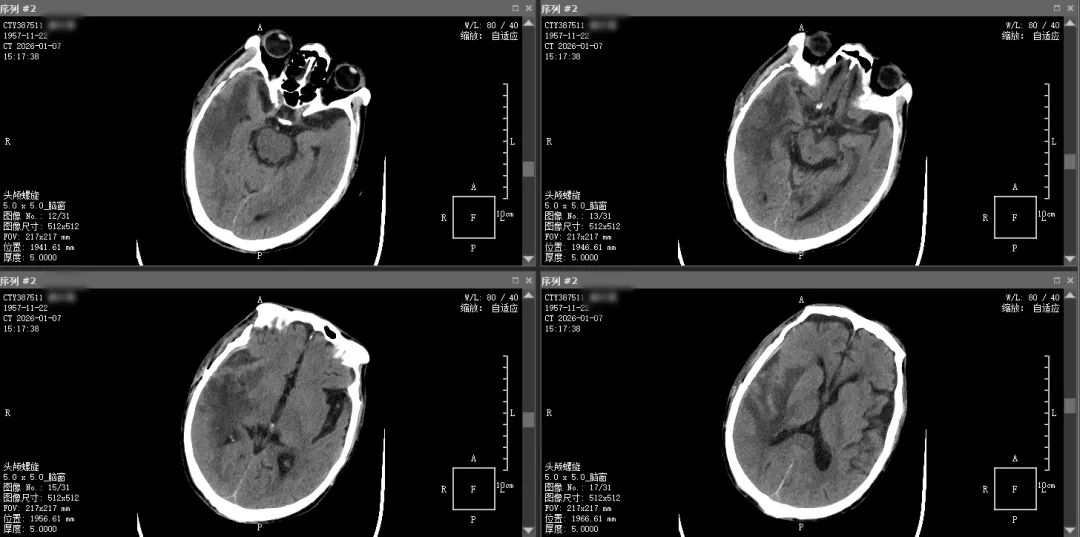

据悉,患者为独居老人,入院前3小时被其侄儿发现倒卧床旁,未盖被褥,周边有呕吐物,已陷入昏迷、呼之不应,伴小便失禁,发病时间疑为夜间。侄儿紧急将其送至我院急诊科,头颅CT检查显示:右侧额颞叶脑出血,血肿量约80mL,右侧侧脑室受压,中线结构移位,已出现脑疝迹象,病情危急,当即以“高血压脑出血”收入神经外科。

▲术前头颅CT影像图